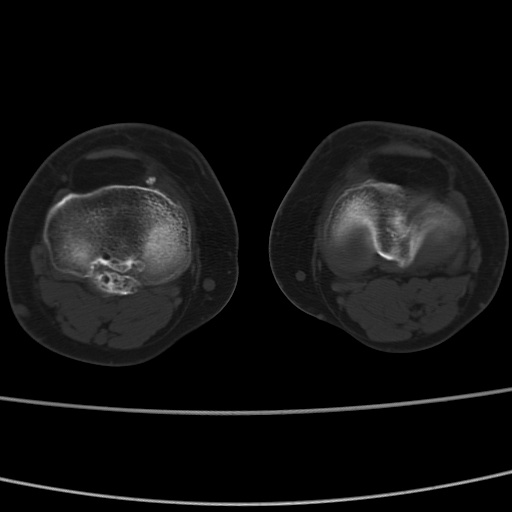

女性,50岁。【请提供患者临床症状体征】

右膝关节退行性改变,关节游离鼠。

右膝关节退行性改变,滑膜黏液囊钙/骨化并游离。

右膝关节退行性改变